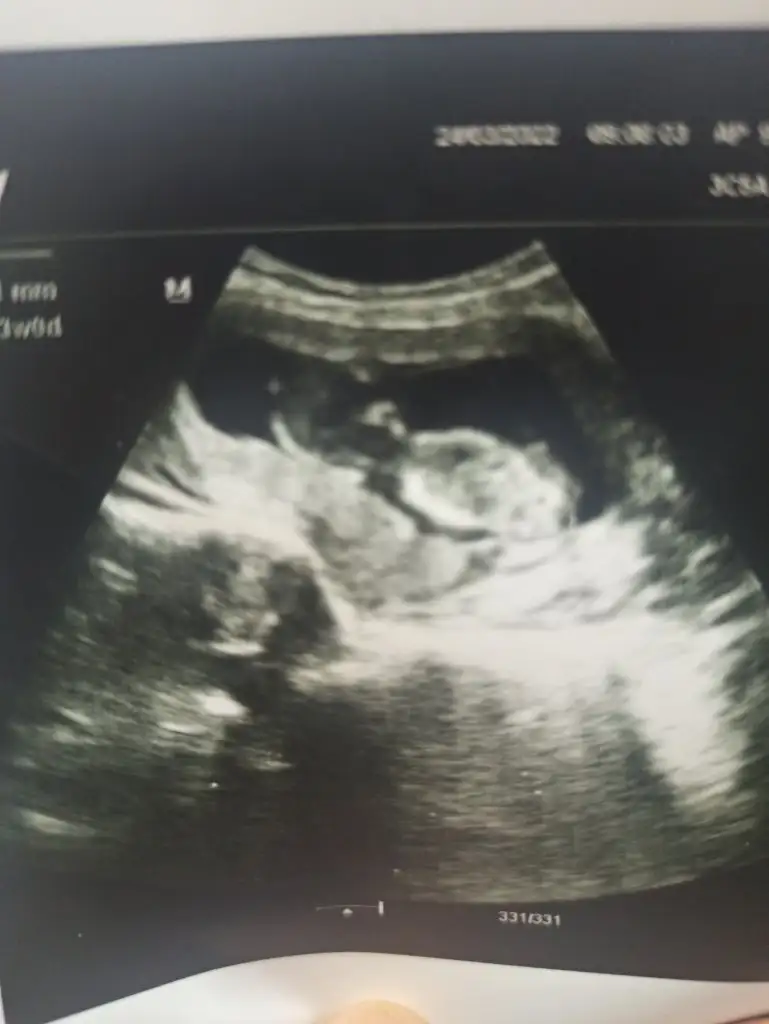

Bana da yorum yapabilir misiniz lütfen

21,7 KB · Görüntüleme: 81